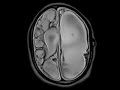

Periventricular Leukomalacia

This study was performed as part of an ultrafast protocol for shunted hydrocephalus which consist of multiplanar T2 haste images are obtained in quick fashion to assess changes in ventricular size. These images demonstrate sequelae of severe hypoxic ischemic injury in the neonatal period which resulted in severe periventricular white matter volume loss with ex vacuo enlargement of the lateral ventricles predominantly on the left. There is gray matter volume loss as well. Part of the hemispheric cortex is preserved as a T2 hypointense residual tissue layer. There is a left-sided VP shunt with the tip located within the left lateral ventricle. In addition to the cerebral atrophy, the brainstem and cerebellum demonstrates volume loss with dilatation of the fourth ventricle and widening of the foramina of Luschka, bilaterally. Overall the patient is microcephalic.